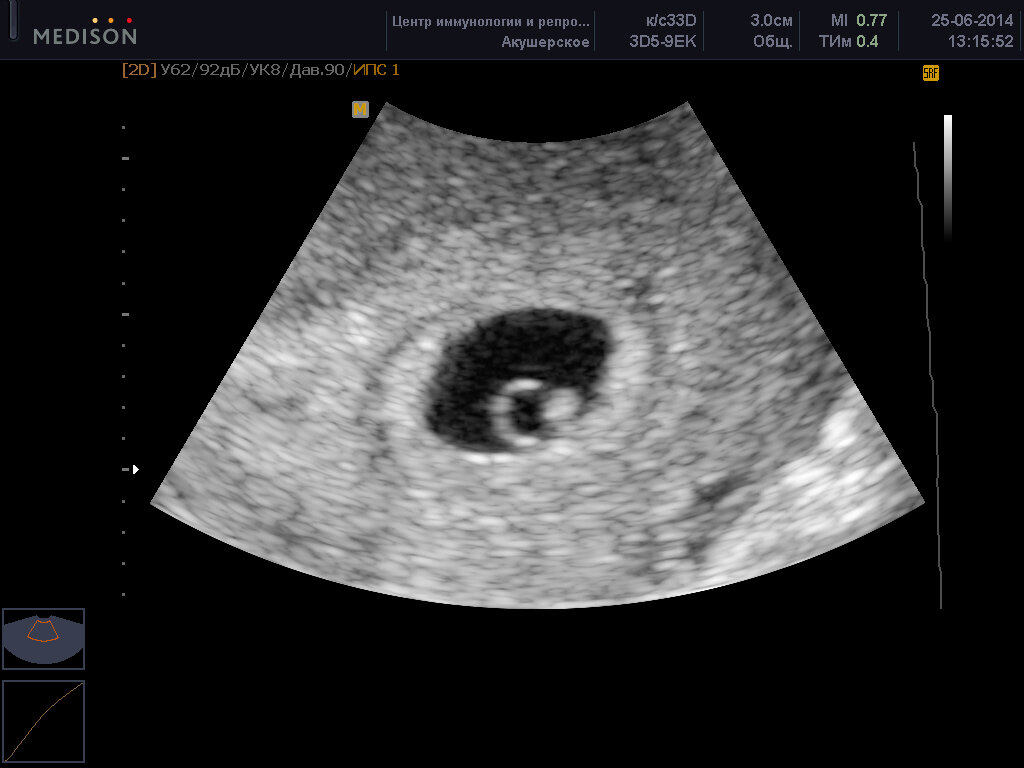

1 способ- снимок УЗИ. Можно распечатать первый снимок вашего малыша и положить его на видное место или спрятать в куртку, кошелек, бардачок машины.